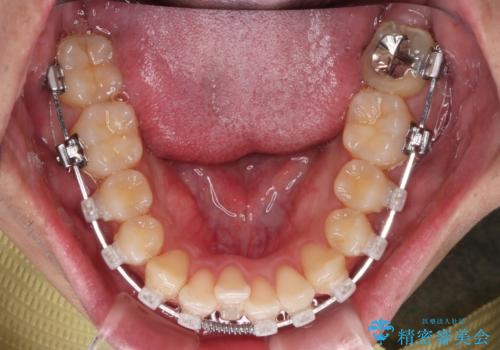

【クリア装置】八重歯とがたつきを綺麗に

- 上の八重歯と下の歯のがたつきを主訴に来院されました。

矯正検査の結果、抜歯はせずに

臼歯を遠心移動させ、歯列をワイヤーで整えることでスペースを確保し、IPR(歯と歯の間を削る処置)を加えて歯並びを綺麗にする治療計画を立てました。

歯の移動にオープンコイルとMI(歯肉に埋入するネジ)を用いました。

非抜歯矯正だったこともあり、1年半以内という短い期間で矯正を終了することができました。

気にされていた八重歯とがたつきが綺麗に改善されました。